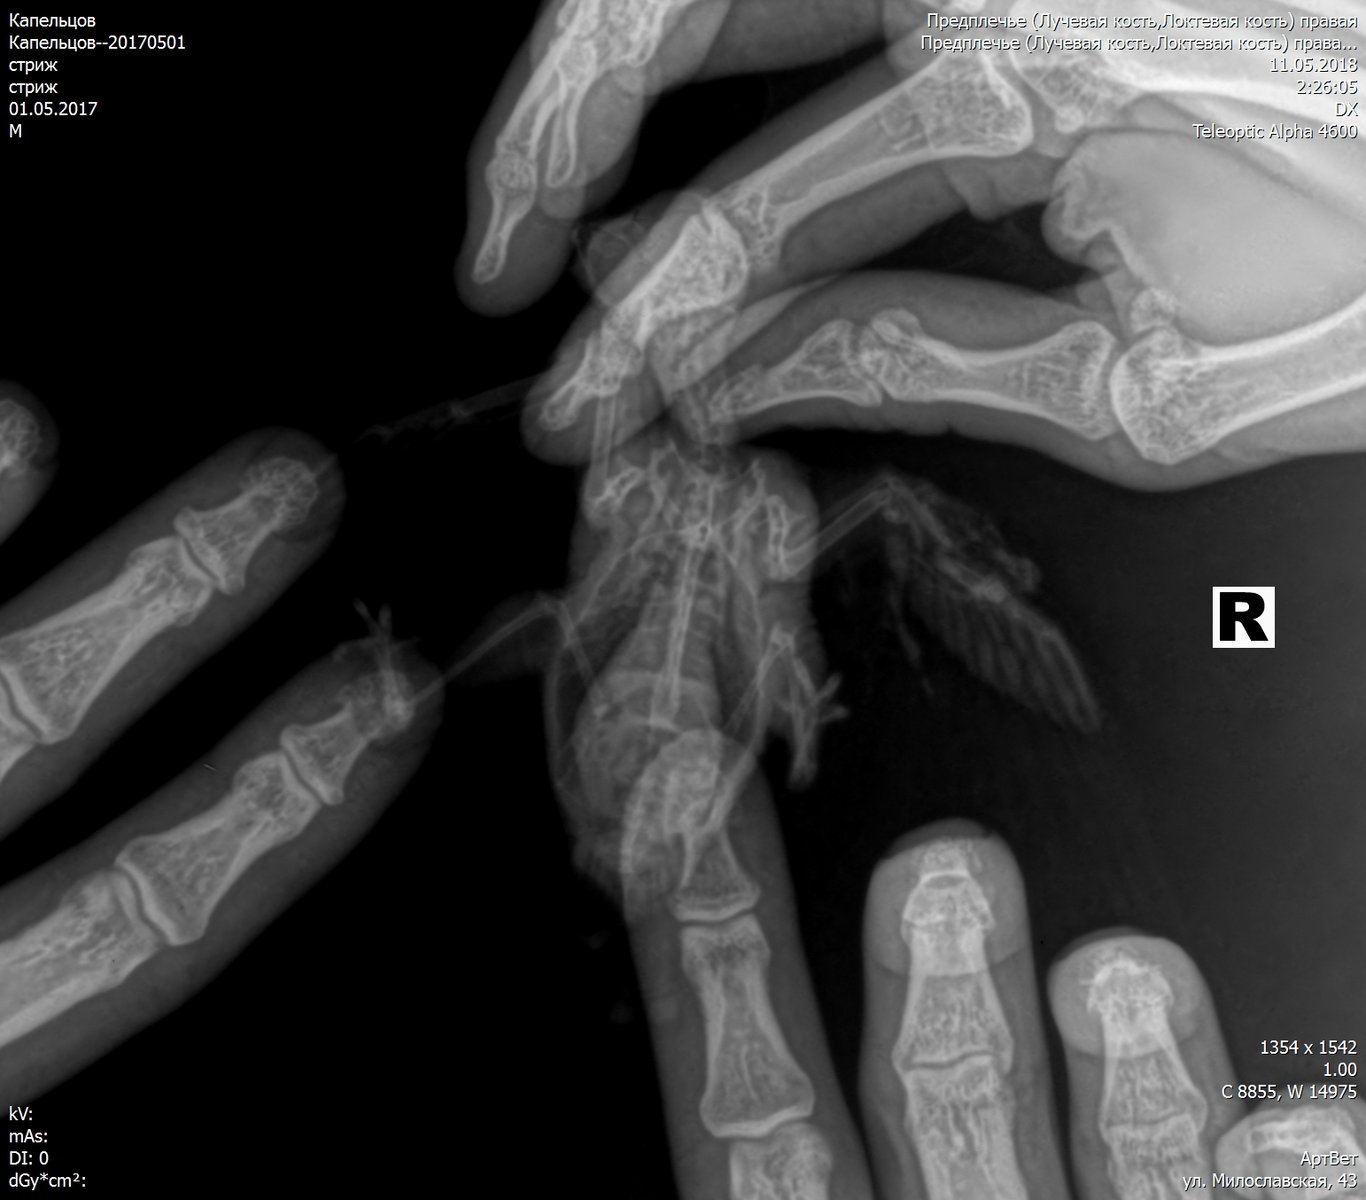

Добрый день. Три дня назад подобрал на улице птицу с неестественным положением правого крыла (о том, что это стриж узнал от ветеринарного врача). Занес в ближайшую ветеринарную клинику, где врач, осмотрев и ощупав птицу (рентгена в клинике не было), сказал, что перелома нет, скорее всего стриж ударился о провод и ему необходимо несколько дней для восстановления. Никогда не имел дел не только со стрижами, но и с птицами вообще, но решил попробовать его спасти. Живет в коробке примерно 30х30х30, кормлю опарышами, так как пока не нашел других насекомых, этот вопрос решу в ближайшее время. Вопрос с питанием отдельная проблема. Больше всего меня беспокоит его крыло. Сегодня свозил птичку на рентген. Врач хотя и увидел перелом, но о лечении птиц знает примерно столько же сколько и я. Даже не знал, как называется сломанная кость (называл её маленькой) Я потом посмотрел в интернете, что это лучевая кость. А локтевую кость называл маховой. Предложил зафиксировать крыло и, прижав крылья к телу, замотал его эластичным бинтом. Приехав домой, я снял эту повязку. Не знаю смогу ли найти ветеринара по птицам, а пока прошу совета и помощи у знающих людей. Есть ли шанс вылечить птицу с таким переломом? Нужно ли её пеленать, как сделал этот врач? Может быть поместить стрижа в маленькую коробочку, чтобы у него не было возможности махать сломанным крылом? В общем, что сейчас делать с птичкой? Спасибо за советы PS На последнем снимке стрижик завернут в эластичный бинт